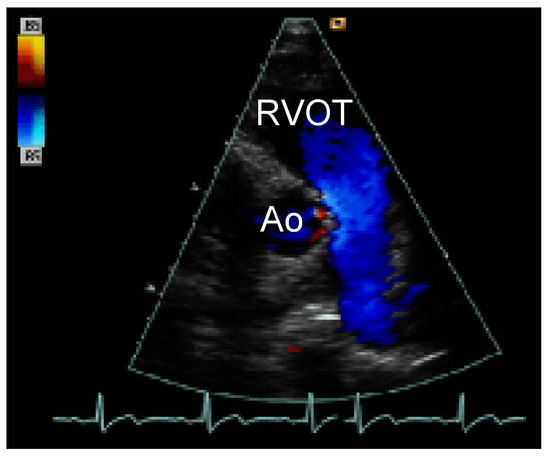

Straight into the Heart: Sinus of Valsalva Injury

by Frank Enseleit, Thomas Largiadèr and Rolf Jenni

Cardiovasc. Med. 2006, 9(6), 238; https://doi.org/10.4414/cvm.2006.01180 - 30 Jun 2006

Viewed by 61

Abstract

A healthy 19-year-old patient was admitted to the emergency department after a knife attack [...] Full article